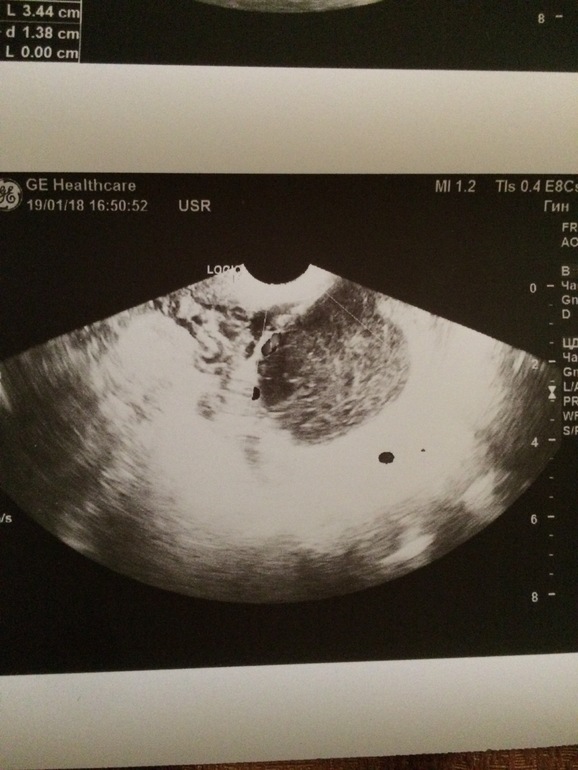

Девочки, кто разбирается? Действительно ли киста ЖТ? Г

поставила под вопросом. Размер смущает.

Сказала что кровоток именно указывает на то что это ЖТ.